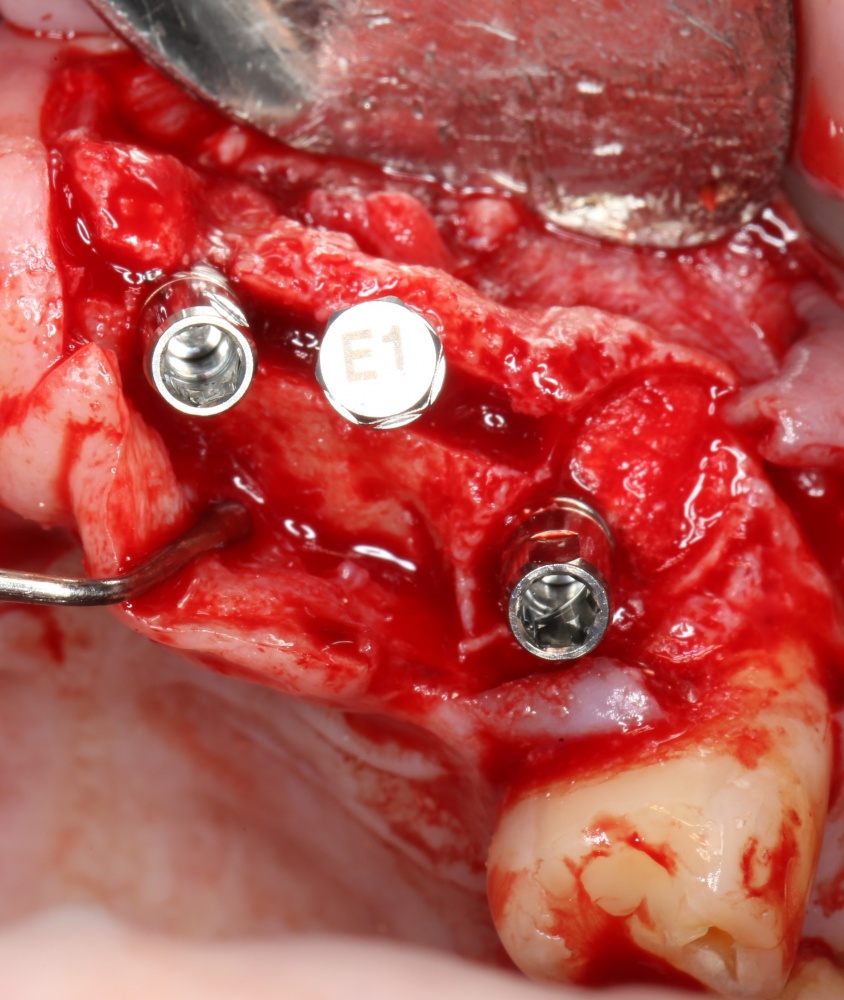

Я зафиксировал костный блок практически без адаптации на несколько винтов. Обрати внимание, что винты находятся в зоне, где не планируется установка имплантатов. Фиксация должна быть надежной, поскольку мне еще предстояла подготовка лунок для имплантатов. Трех винтов для этого вполне достаточно.

Дальнейшая адаптация костного блока свелась к сглаживанию острых краев. После чего я приступил к подготовке лунок и установке имплантатов.

Установка имплантатов.

Напомню, что для этой работы я выбрал субкрестальные имплантаты Ankylos C/X. Они прекрасно сочетаются с любым методом остеопластики.

Я не планирую установку супраструктур или коронок, поэтому на уровень первичной стабильности можно положить болт. Даже наоборот — чем меньше крутящий момент при установке, тем лучше. Для имплантатов Ankylos и подобных им, это особенно важно. В общем, момент силы при установке — не более 10-15 Нсм.

Ремарка: имплантаты с предустановленными имплантодержателями хороши тем, что с ними легко контролировать позиционирование имплантатов. В случае с Ankylos С/Х - еще и крутящий момент. Имплантодержатель должен отсоединяться от имплантата с легким щелчком. Если его клинит, и тебе приходится прикладывать для этого усилия, то ты, однозначно, превысил момент силы во время установки имплантата. Следовательно, жди проблем.

Глянем на то, что получилось:

Осталось адаптировать костный блок (убрать острые края), проверить его фиксацию и, при необходимости, добавить винты. Десятисекундное дело.